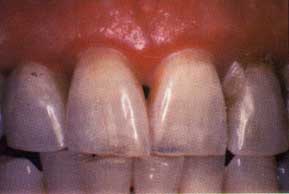

Figure 8a. Atrophic gingival lichen planus in a 56-year-old female. Erythema of the attached gingiva, especially along the free gingival margin. Figure 8b. Custom steroid carrier.

Figure 8c. Partial resolution of the gingiva after four weeks of nightly topical steroid applications in the custom carrier. Note the overall improvement in gingival tone and the "breaking up" of the erythema of the free gingival margin.

Oral lichen planus is often identified by the presence of fine reticular white lines (striae of Wickham) on the lateral borders of the tongue, buccal mucosa, and gingiva (Figure 6). However, striae are not always present, especially in the ulcerative form of the disease; therefore, definitive diagnosis is made by biopsy. Although prospective studies have failed to demonstrate that lichen planus is a premalignant disorder, it is recommended that all patients exhibiting this condition intraorally, particularly those who have had the ulcerative form, receive long-term follow-up (Figure 7).26-28

Occlusive steroid therapy using custom-made flexible mouth guards to localize fluocinonide gel is extremely effective in controlling the gingival lesions of lichen planus.32-33 Fluocinonide 0.05 percent gel is applied to the mouth guards, and patients are instructed to wear them for 30 minutes per application. Therapy can be instituted with a regimen of four applications daily, preferably after meals and at bedtime. The frequency of daily use depends on the response of the lesions. Long-term control of persistent lesions can often be achieved with a 30-minute application every other evening.